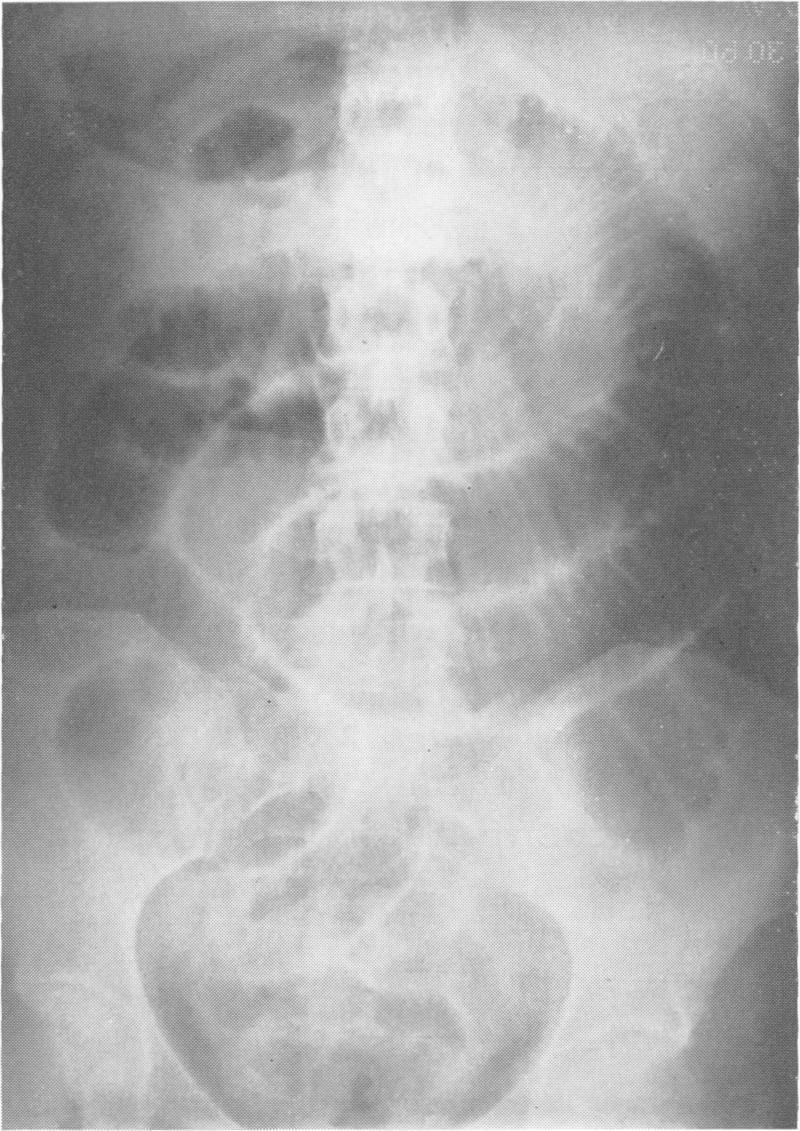

Mechanical small bowel obstruction due to acute appendicitis: review of 10 cases.

Ann Surg. 1966 Jul;164(1):157-61. doi: 10.1097/00000658-196607000-00018.

https://cdn.ncbi.nlm.nih.gov/pmc/blobs/e6ae/1477191/2986d73eaad0/annsurg00445-0167-b.jpg

https://cdn.ncbi.nlm.nih.gov/pmc/blobs/e6ae/1477191/d223adce781b/annsurg00445-0167-a.jpg